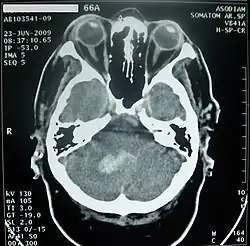

Кровоизлияние в мозжечок обычно проявляется головокружением, тошнотой и повторной рвотой при сохранении сознания. Больных часто беспокоит головная боль в затылочной области, у них обычно выявляются нистагм и атаксия в конечностях. При возникновении мозжечково-тенториального смещения или вклинении миндалин мозжечка в большое затылочное отверстие развивается нарушение сознания вплоть до комы, геми- или тетрапарез, поражения лицевого и отводящего нервов[43].